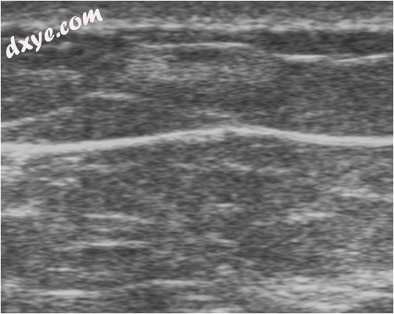

侵袭性小叶癌(ILC)

ILC是浸润性导管癌后第二种最常见的乳腺癌形式,其特征是肿瘤细胞分别或链中侵入乳腺实质。最常见的乳房X线照相外观是针刺质量,但观察到不对称密度和结构破坏的频率高于IDC(图16)。至于IDC,超声波通常显示出低回声肿块,具有毛刺边缘和后部衰减。相反,ILC可呈现非典型特征,例如缺乏明确定义的肿块或高回声性。 ILC中的高回声呈现频率是IDC的10倍[20]。

图16

侵袭性小叶癌。乳房X线摄影,AP视图,显示右上内象限(箭头)的边缘不规则的肿块。 b超声显示不规则,边界不良,垂直方向,高回声和部分减弱的病变